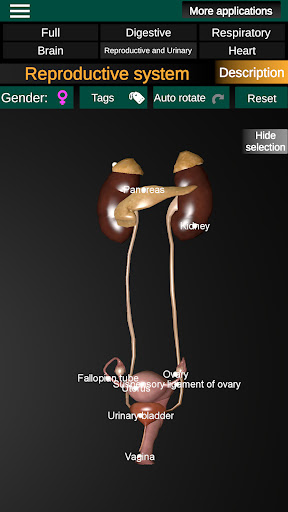

* Sistem reproduksi, yang meliputi organ reproduksi pria dan wanita.

* Bandingkan organ pria dan wanita.